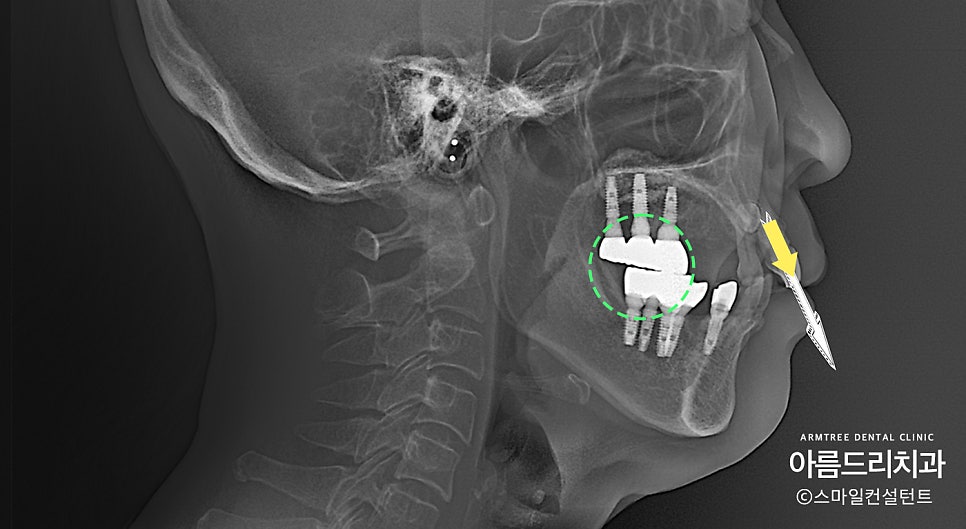

앞니 2개가 툭~ 튀어나와 있습니다.

바로 옆치아가 발치됐고 뼈가 흡수돼서

상대적으로 더 튀어나와 보이네요.

더군다나 입이 튀어나온 사람들은

평소에 입술이 잘 다물어지지 않습니다.

입술이 잘 다물어져야 입 속이 마르지 않고

발음도 좋아지고 편안해집니다.

앞니 각도가 많이 뻐드러져 있습니다.

어금니쪽은 교합(초록색)을 제대로

안 맞춰놔서 위 아래가 뜨는 게 보이는 상태!